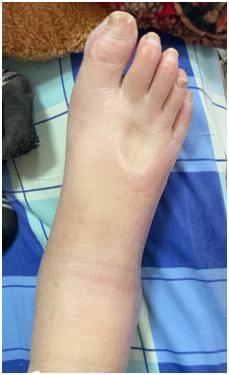

接诊的结核外科钟方明医师表示 , 由于张大妈原本就患有糖尿病、肾病等疾病 , 基础体质偏差 , 再加上患了结核性心包炎 , 来就诊时走两步就气喘吁吁 , 脸部及下肢的水肿都十分明显 , 轻轻一按就是一个“坑” 。

除了缩窄性心包炎的症状明显 , 中心静脉压测量结果同样显示张大妈的静脉压力很高 。 钟方明认为 , 她需要尽早手术 , 解除心脏压力 。